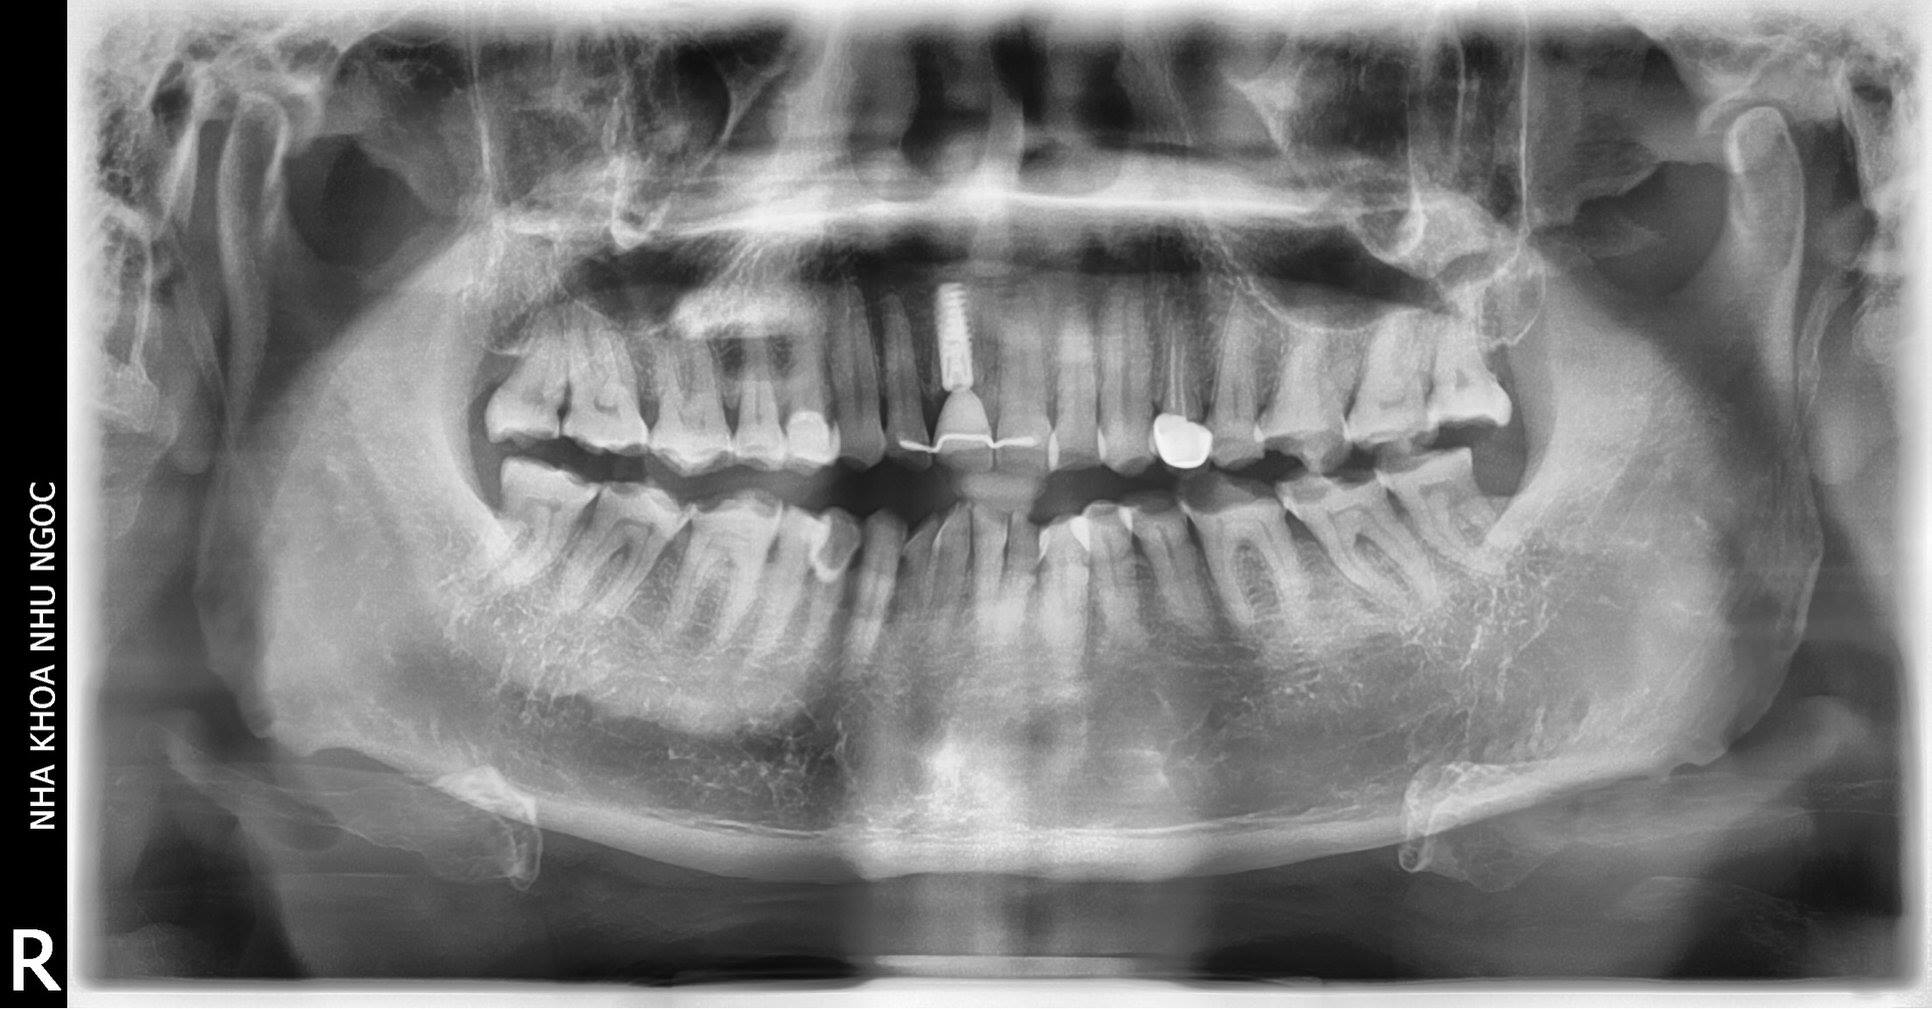

Thăm khám và chẩn đoán hình ảnh 3D

Bác sĩ tiến hành kiểm tra tổng quát khoang miệng, chụp phim CT Cone Beam 3D để đánh giá mật độ xương hàm, vị trí mất răng và lập kế hoạch điều trị chi tiết.

Sử dụng phần mềm mô phỏng kỹ thuật số để xác định vị trí, hướng và kích thước trụ Implant, đồng thời tiên lượng kết quả phục hình sau cùng.